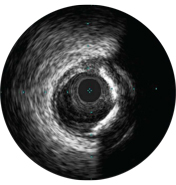

На мальаппозицию указывает наличие крови за стратами стента. При визуализации с использованием режима ChromaFlo кровоток окрашен в красный цвет для простого выявления мальаппозиции и других особенностей просвета.

Существует статистика, что частота возникновения краевых диссекций после имплантации стента с лекарственным покрытием составляет 10%, при этом практически 40% из них не выявляются при ангиографии. Угол диссекции ≥ 60° или MLA <4 мм2 указывают на высокую степень диссекции, требующую лечения. Такие характеристики связаны с более высокой частотой возникновения раннего тромбоза стента 2.

Степень раскрытия стента является предиктором тромбоза стента и рестеноза. Целевая минимальная площадь стента после ЧКВ может включать ≥ 80% референсных площадей просвета, 6 мм2 для стентов с лекарственным покрытием в сосудах, не относящихся к ЛКА, или другие критерии в зависимости от типа ЧКВ. ВСУЗИ помогает задокументировать полученные результаты2.